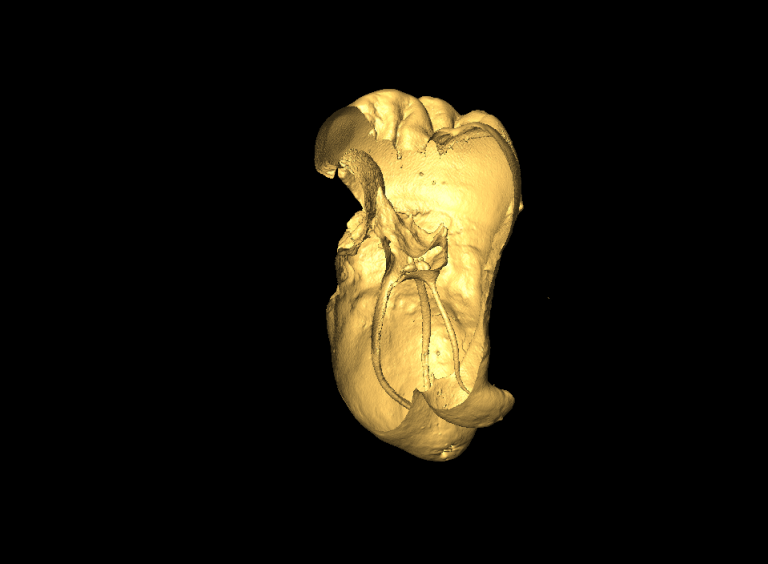

Milabs CT is capable of fast scanning and ultra-high-resolution scanning under low-dose X-rays, and the highest resolution can reach 10um.

- 3D surface image simulation of teeth